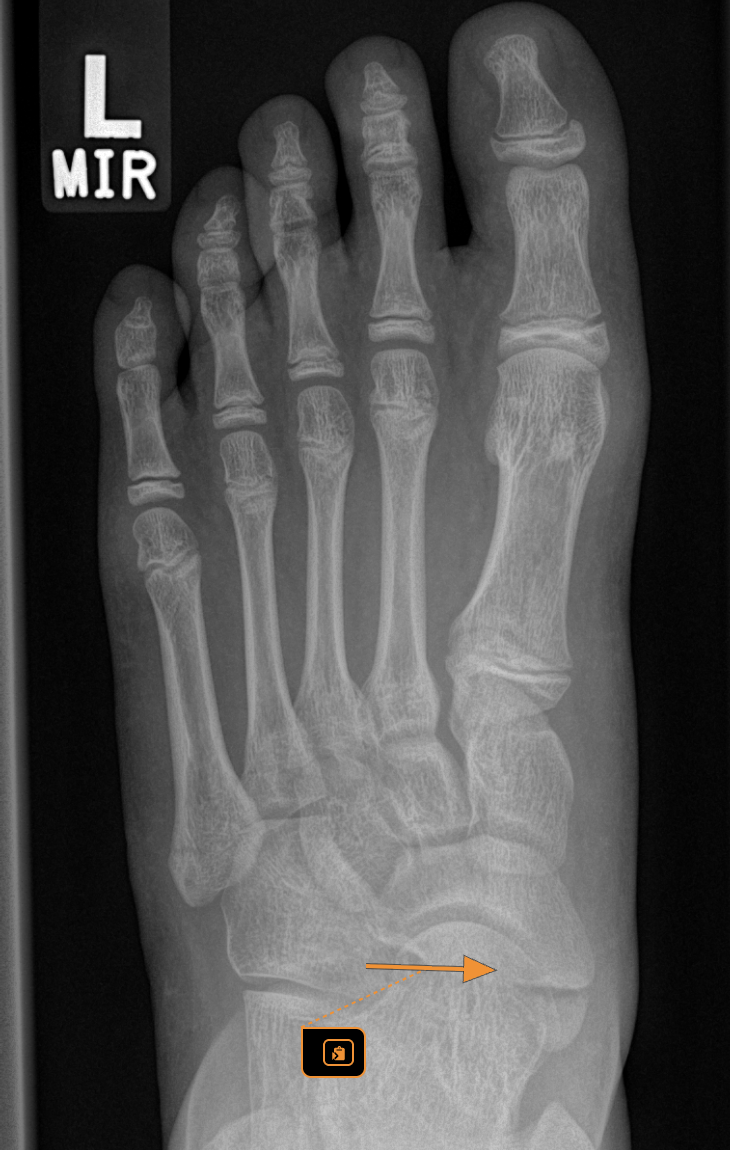

Accessory navicular is a common developmental variation where an extra piece of bone or cartilage is present on the inside of the foot near the arch. This bone sits next to the navicular bone which plays an important role in foot structure and function. While many children with an accessory navicular never experience symptoms others can develop pain swelling and difficulty with walking or sport.

A thorough assessment includes looking at foot posture walking pattern footwear and activity levels. Imaging such as x ray may be used to confirm the presence of the accessory navicular and rule out other causes of pain. Importantly we assess how the foot functions not just what it looks like on imaging.